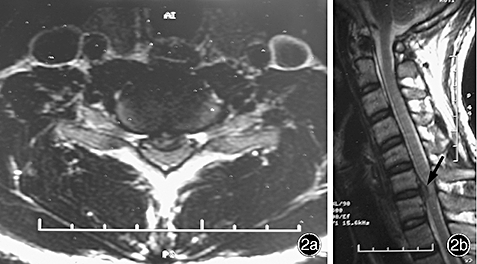

The images below are from just three of the many published case studies showing severe bulging discs in the neck and lower back that the nervous system was able to heal naturally:

Case Study 2: